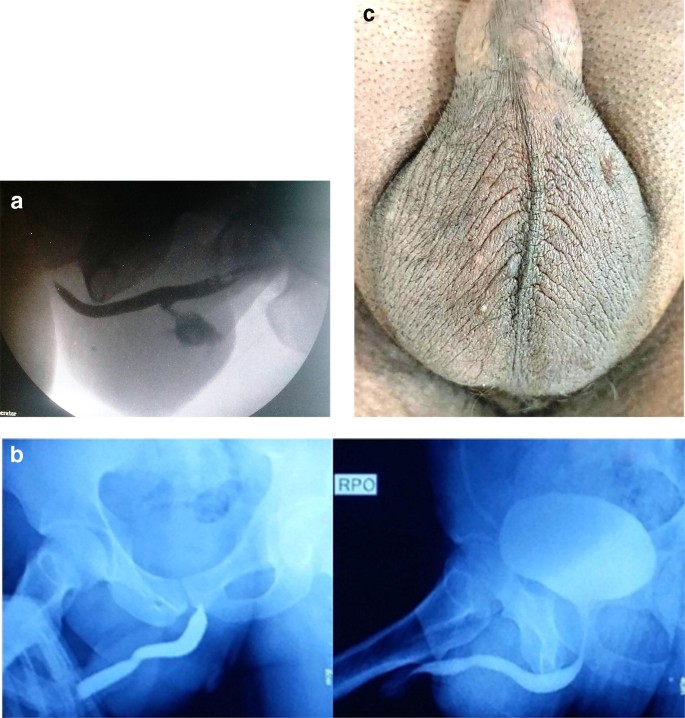

Vasectomy Causing Urethrocutaneous Fistula A Rare Complication Springerlink